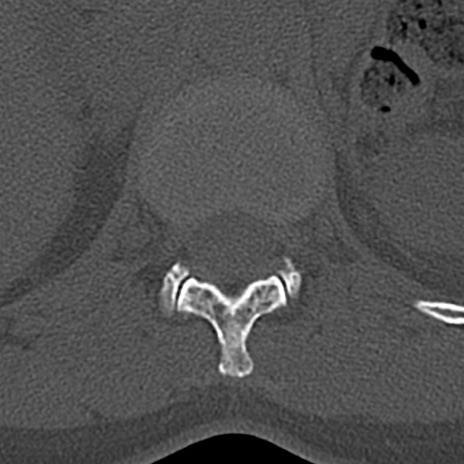

腰椎CT

横断像と矢状断像